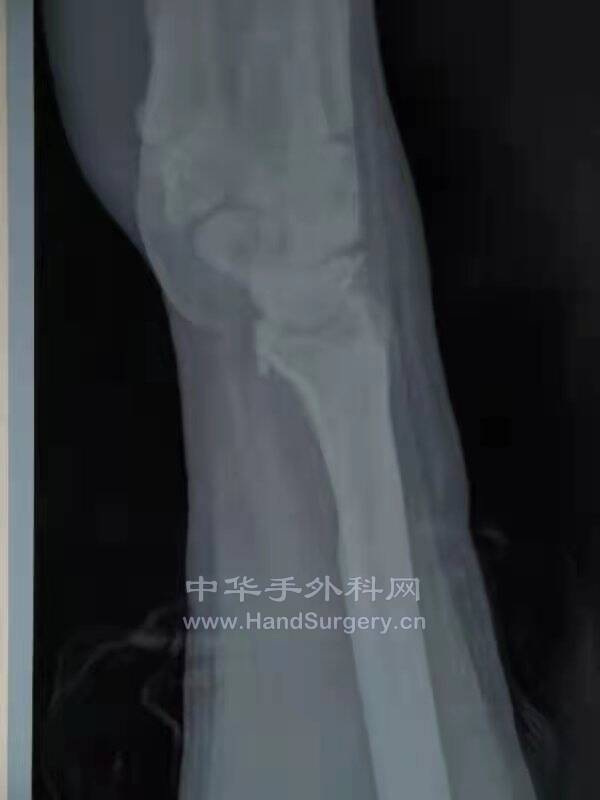

舟月进行性塌陷SLAC

舟骨不愈合进行性塌陷SNAC

临床上,我们可以把舟骨不愈合造成的关节炎的发展过程分为四期。

Ⅰ期特点是桡骨茎突处关节炎表现,骨赘形成;

Ⅱ期表现是桡舟关节骨性关节炎;

Ⅲ期,关节炎累及舟头和头月关节;

Ⅳ期为全腕关节炎(桡月关节除外)。

这一发展过程称为“舟骨不愈合进行性塌陷”,即SNAC腕。